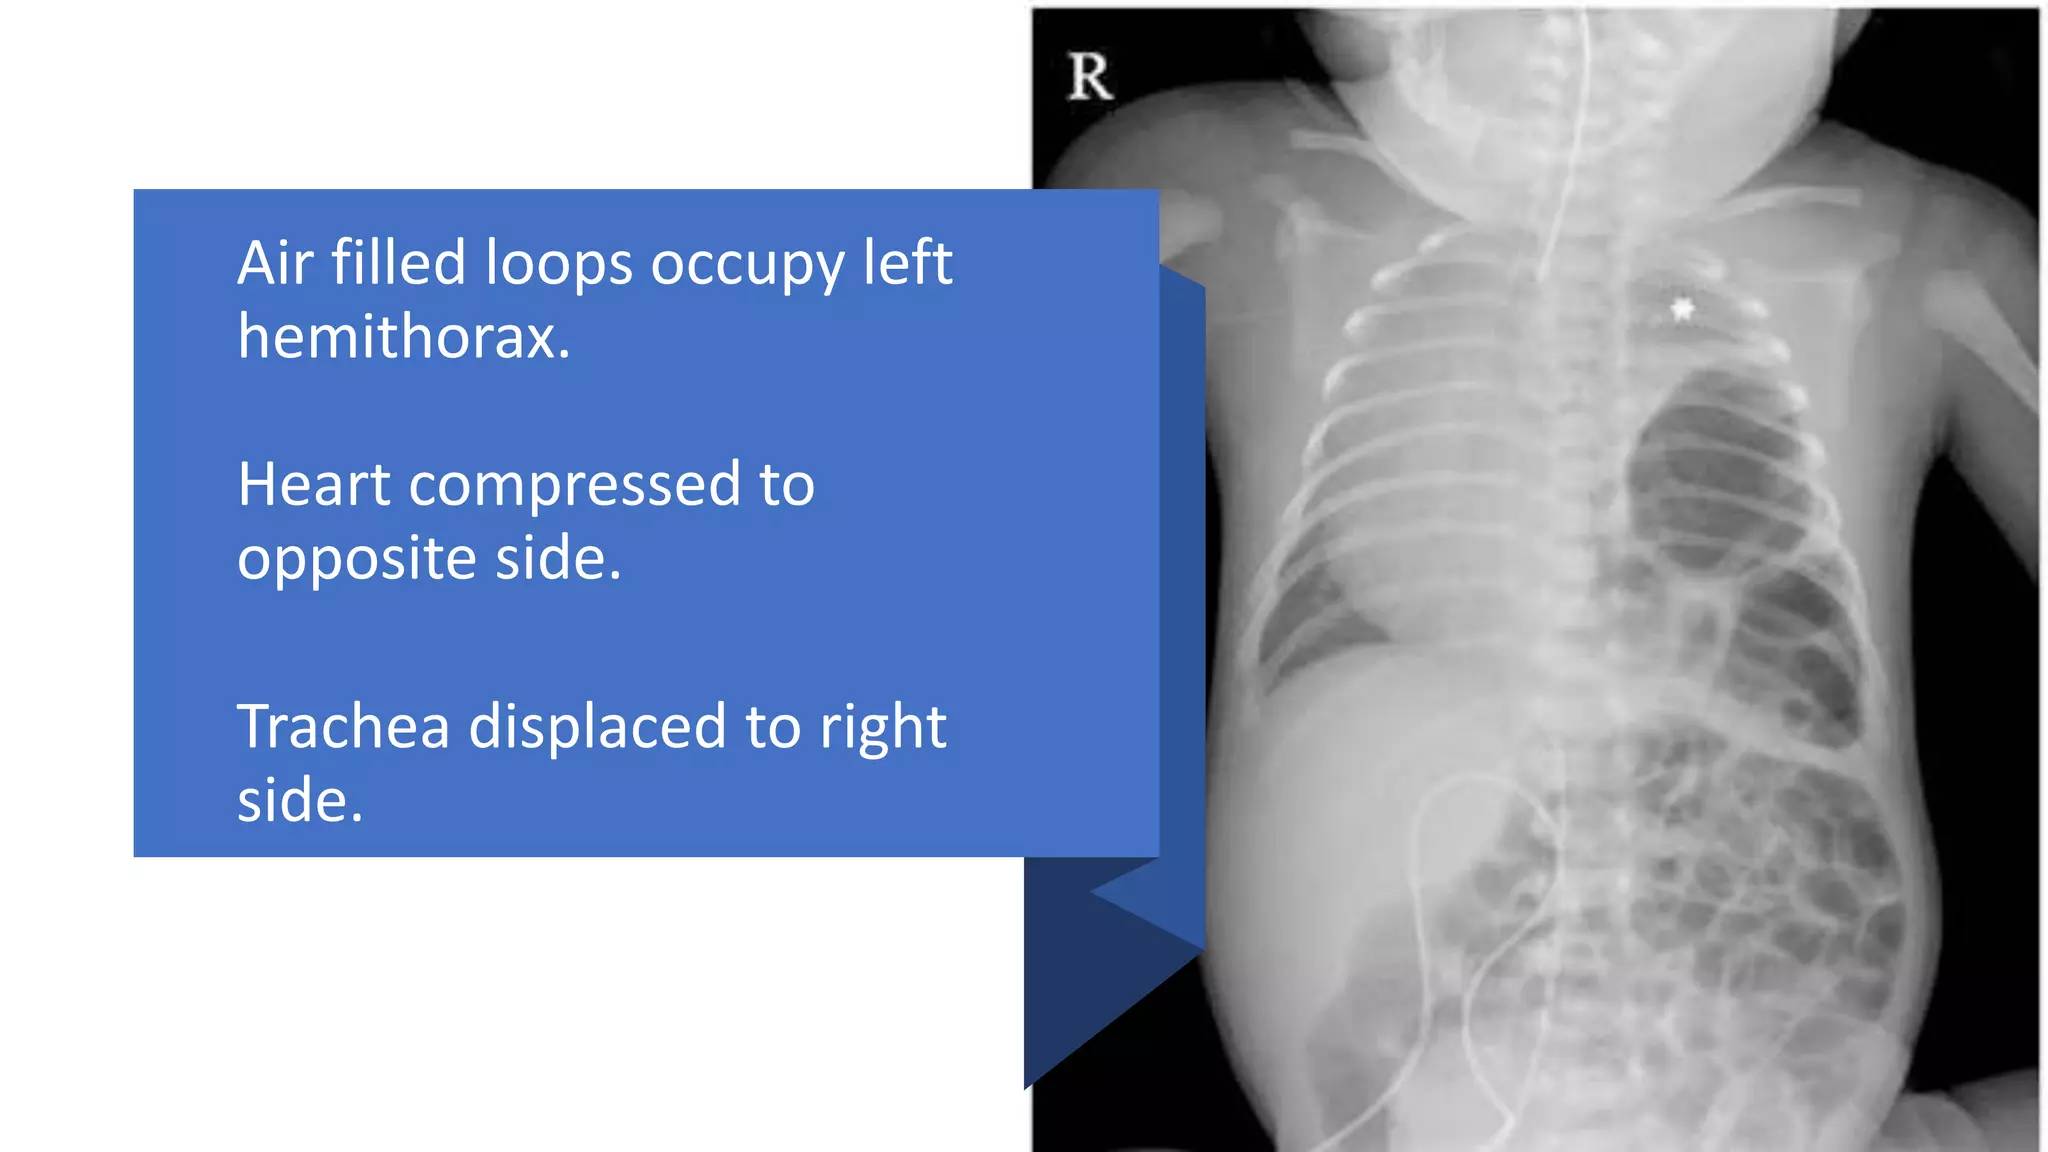

This document provides an overview of neonatal chest x-rays, including when they should and should not be performed, what a normal x-ray looks like, common positions of tubes and catheters, and common causes of respiratory distress in neonates. It discusses the appearance of a normal chest x-ray as well as conditions like respiratory distress syndrome, transient tachypnea of the newborn, meconium aspiration syndrome, and pneumonia. Surgical conditions like diaphragmatic hernia and esophageal atresia are also reviewed.